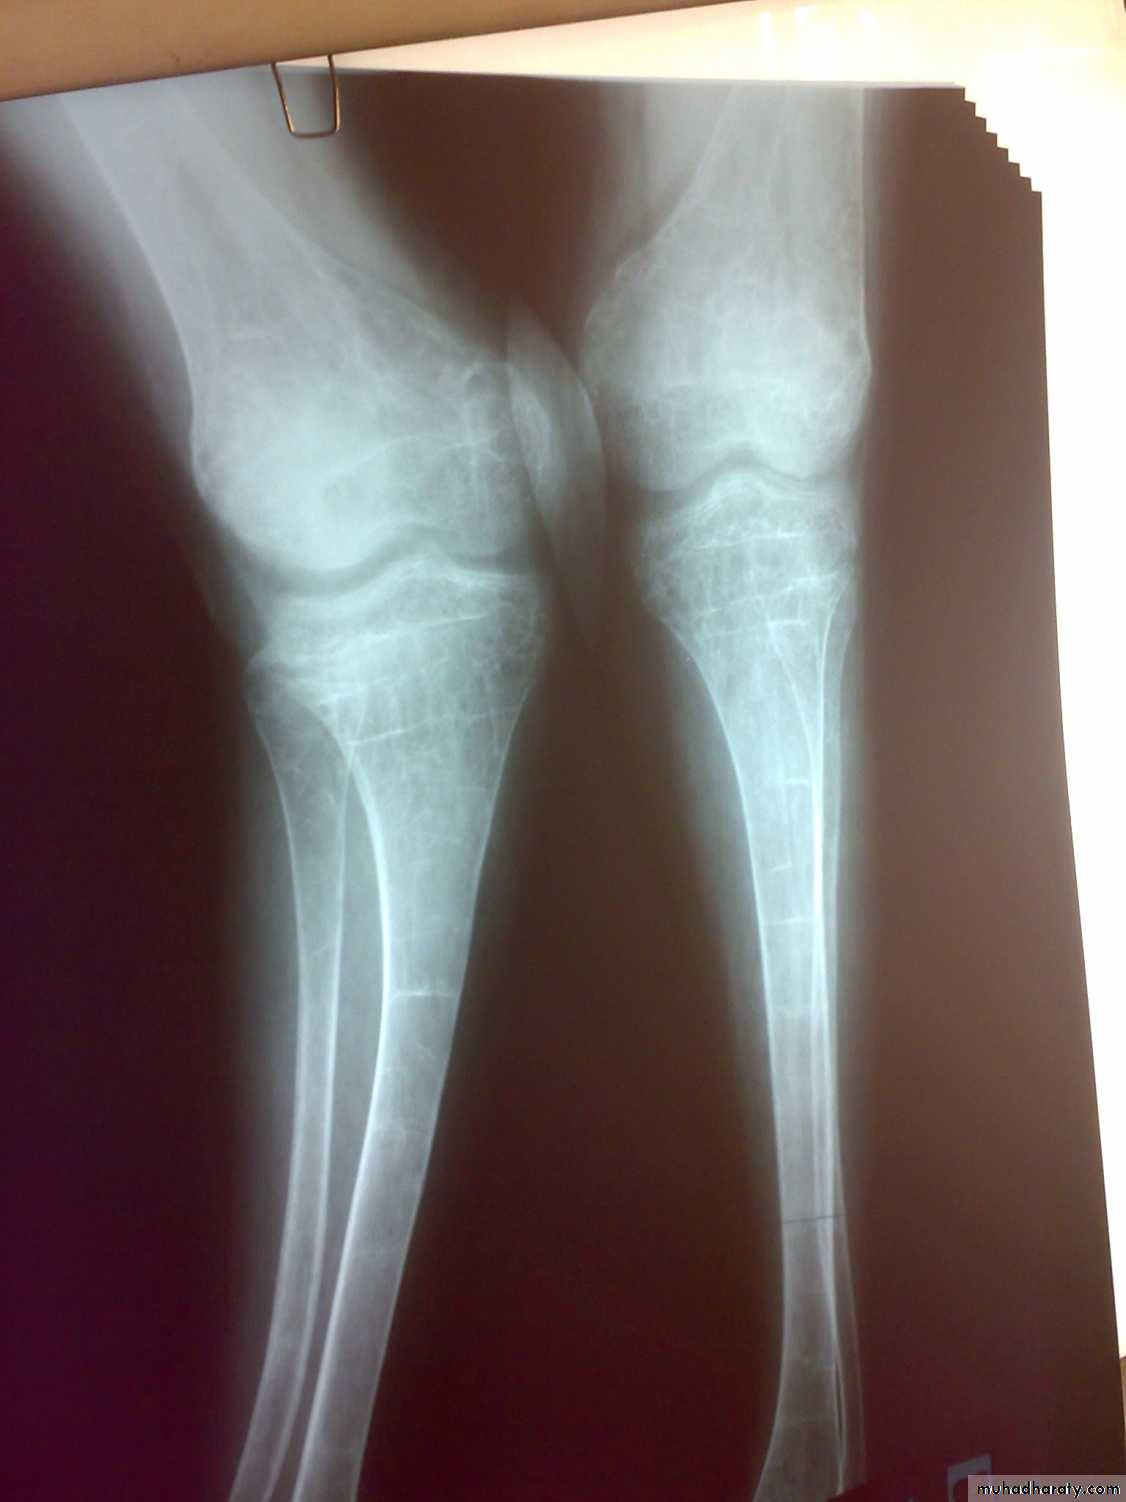

Osteomalacia and ricketsinadequate mineralization of bone

Bone tissue throughout the skeleton is abnormally calcified and therefore soften ( Osteomalacia).

Rickets and Osteomalacia is same disease.

Losser’s zone